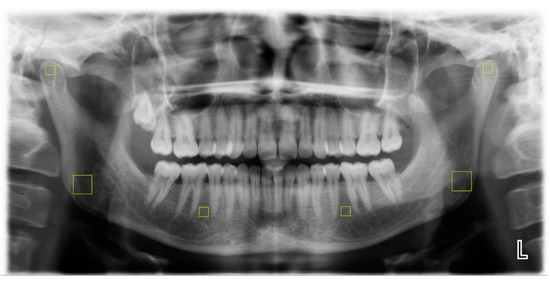

Six regions of interest (ROIs) were specified for computing fractal dimensions (FDs) by two trained dentists (KTT and KB): two 50 × 50 pixel ROIs in each superior section of the condyle that were not in contact with cortical bone, two 100 × 100 pixel ROIs in each gonial area on the angle bisector of two lines crossing the inferior border of the mandible and the posterior border of the mandibular ramus without contact with the cortical bone, and two 50 × 50-pixel ROIs in the region between the second premolars’ apex and the mesial apex of the first molars without contact with the dental structure or lamina dura (Figure 1). The observers repeated the analysis with 20% of the images 1 month after the initial assessment.

Figure 1.

Selection of ROIs (marked by yellow squares).